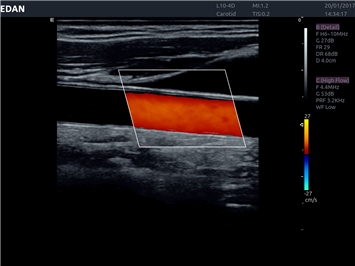

EDAN Acclarix LX4 представляет собой инновационную ультразвуковую систему, построенную на усовершенствованной платформе Acclarix. Сочетание высокого качества визуализации с интеллектуальным рабочим процессом делает эту систему оптимальным выбором для клиник, ценящих эффективность и экономичность.

• Автоматическое измерение толщины интима-медиа

• Сосудистой диагностики

Недопплеровская визуализация кровотока:

Да

Направленный энергетический допплер:

Цветовой допплер: